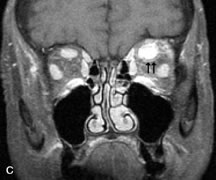

Metastatic Tumors

Breast carcinoma metastatic to the orbit has been demonstrated to be hypointense to the surrounding orbital fat on T1-weighted studies and hyperintense on T2-weighted images and has an affinity to the extraocular muscles (Fig. 20).50,64 The MRI characteristics of prostate carcinoma metastatic to the orbit have been described as involving the greater and lesser wing of the sphenoid, orbital roof, and optic canal. Diffuse bone hypertrophy with isointense or slightly hyperintense tissue on T1-weighted images represents the osteoblastic carcinomatous bone infiltration. Contrast enhancement is variable on T1-weighted and fat-suppressed images.65

Fig. 20. A. T1-weighted MR scan demonstrates nodular enlargement of both medial rectus muscles (arrows). B. T1-weighted fat-suppressed contrast-enhanced scan confirms the presence of small metnstatic deposits within the muscles (open arrows).